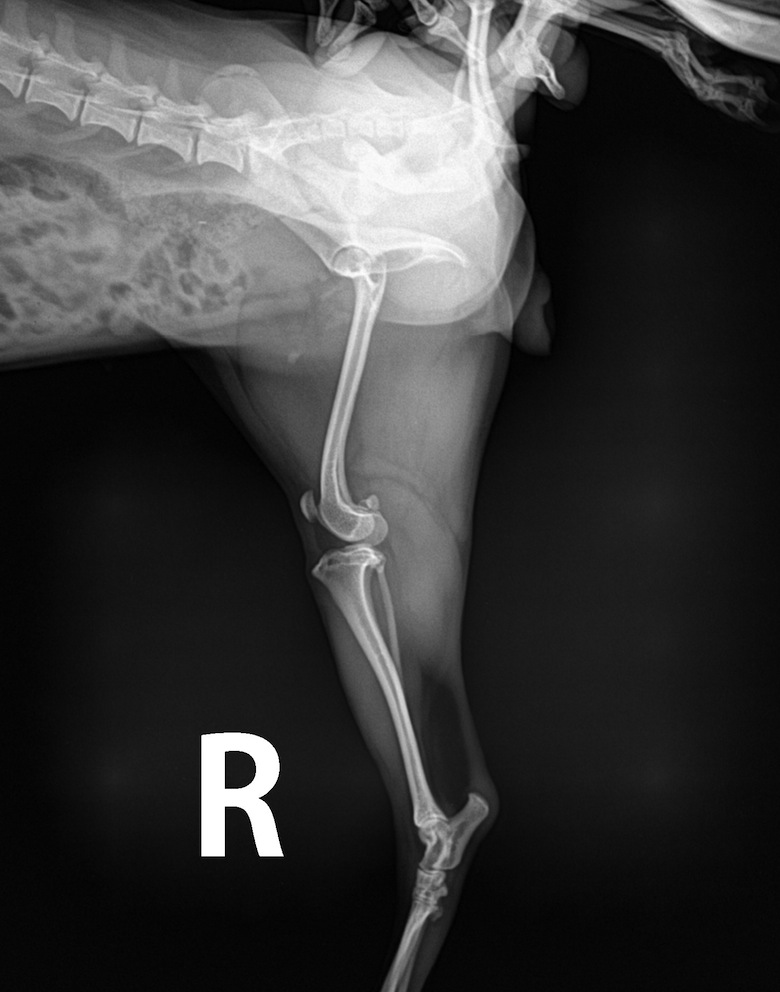

Bbang’s pic

in

A picture of $60, even without developing on paper.

Anyway, the pic looks cool also with the ‘R.’